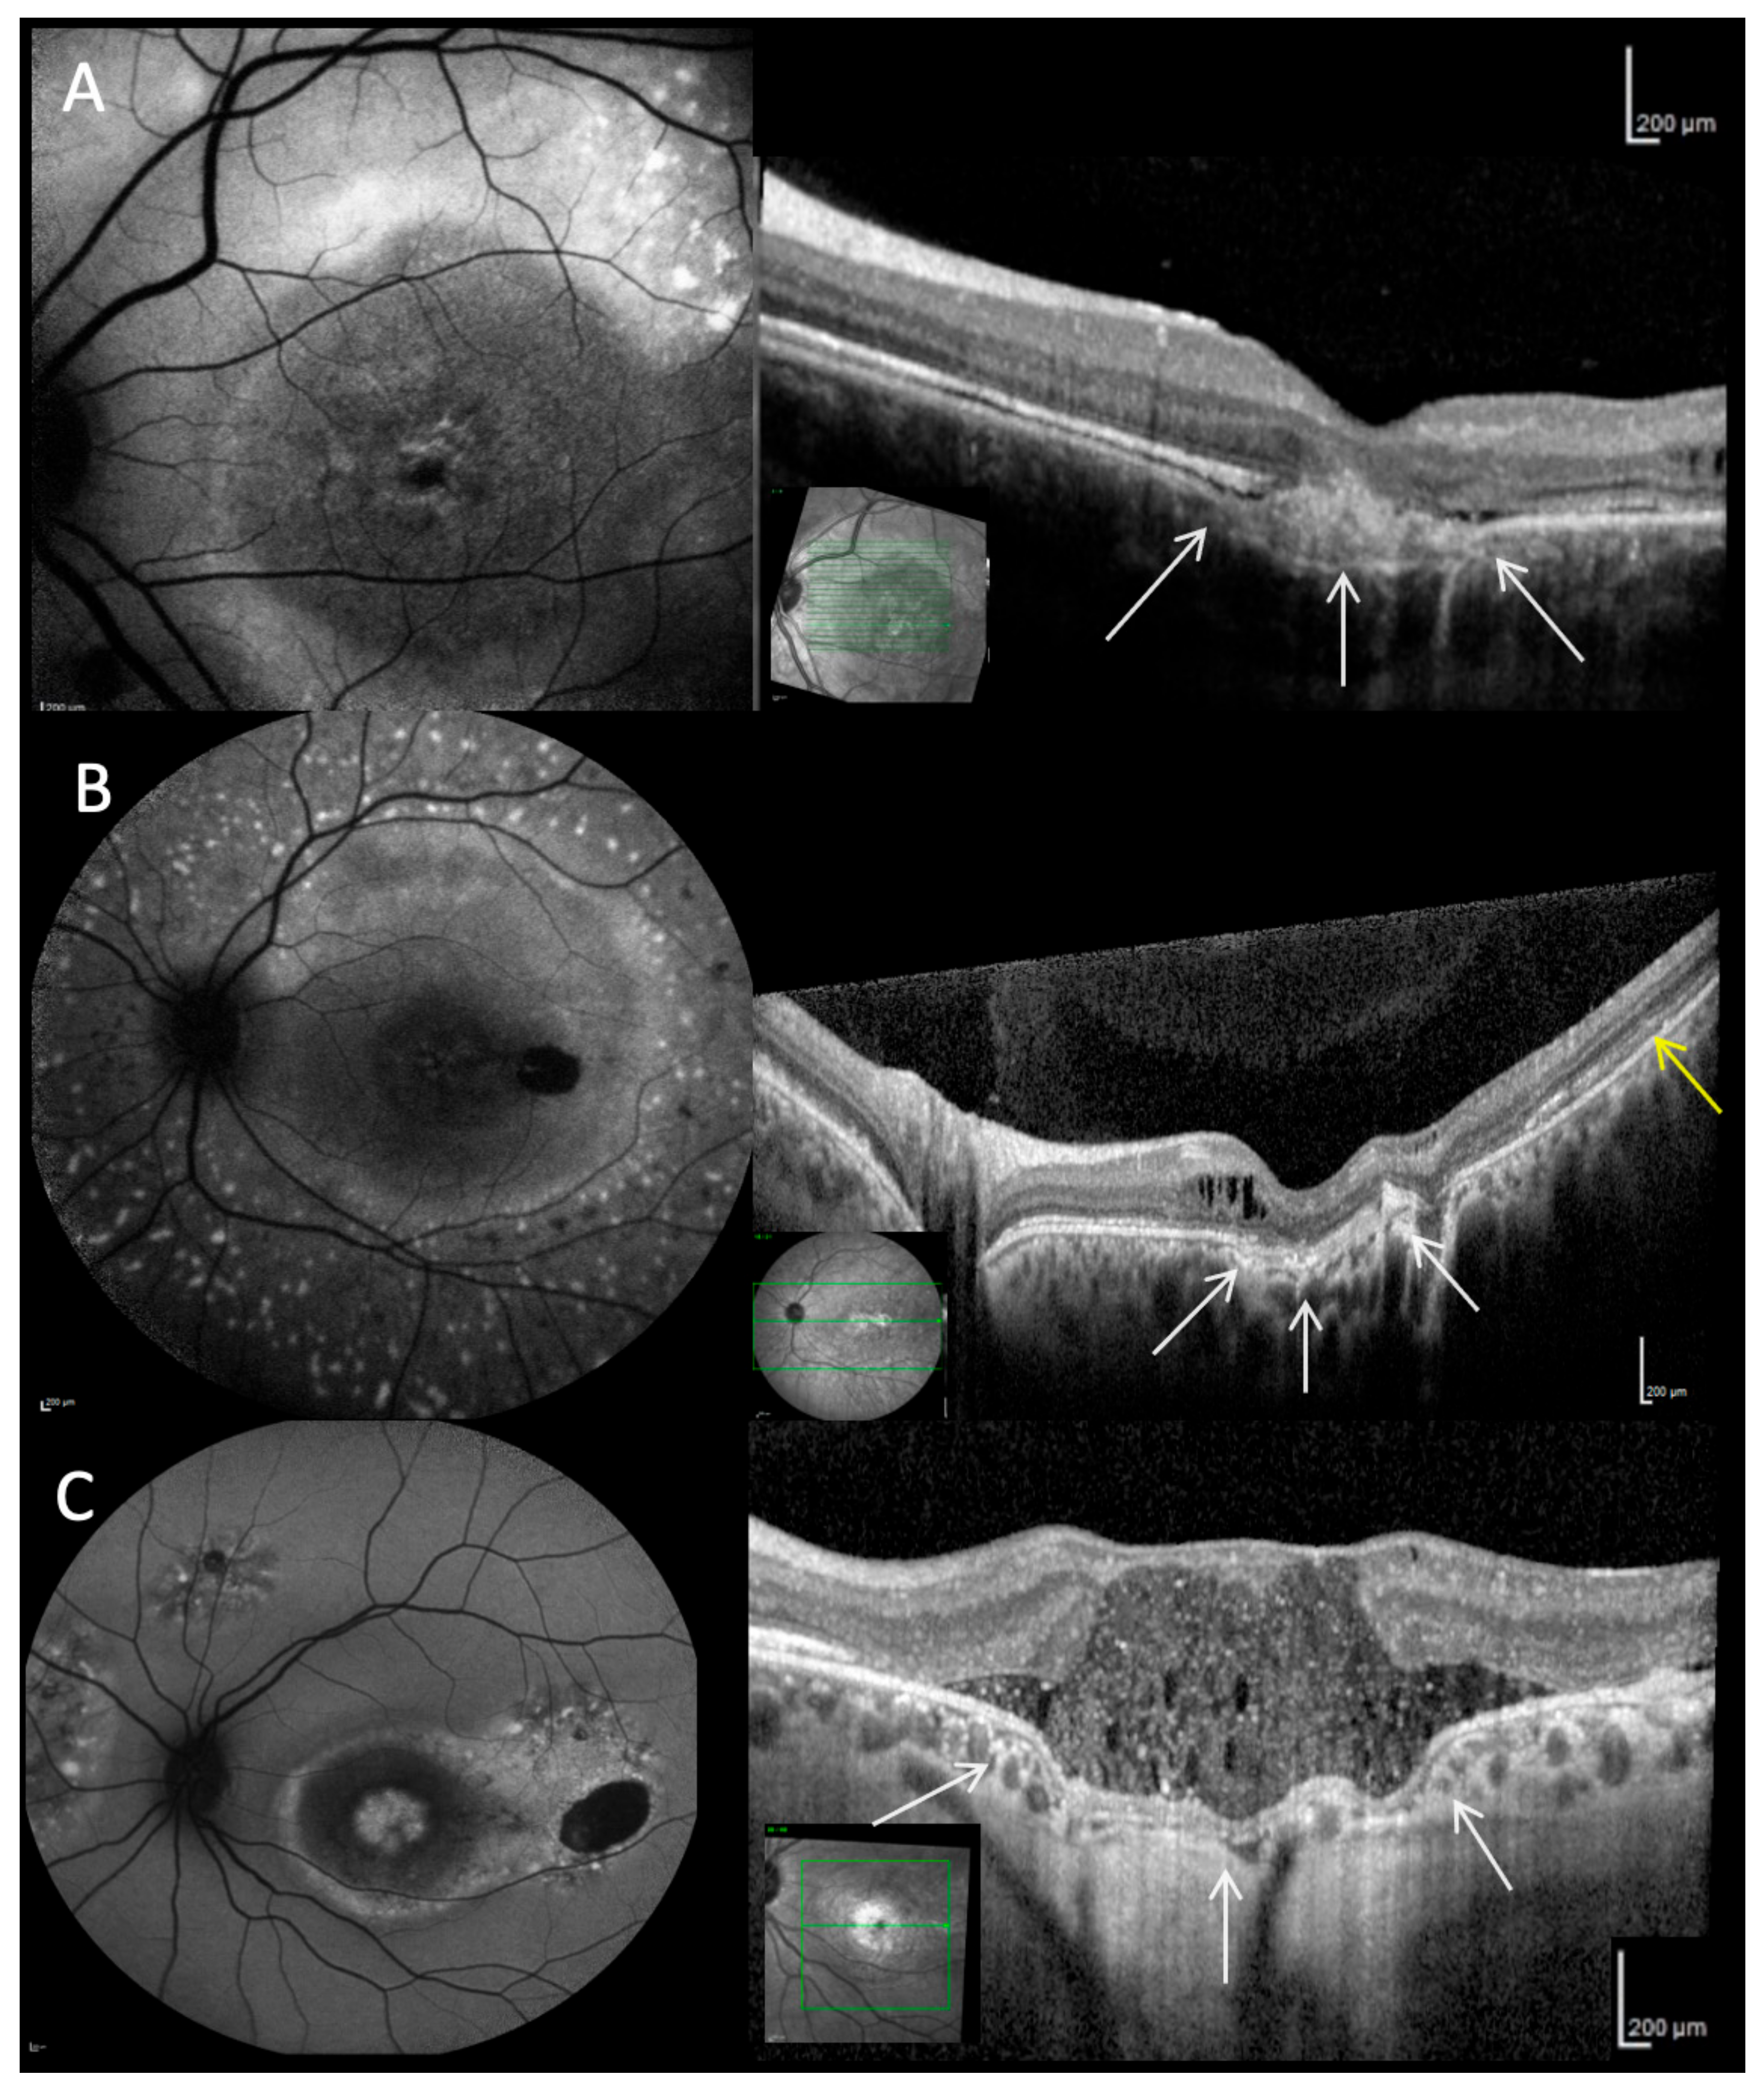

2.2. Clinical Findings

2.3. Clinical Phenotypes

2.4. Fundus Autofluorescence

2.5. Optical Coherence Tomography

2.6. Fluorescein Angiography